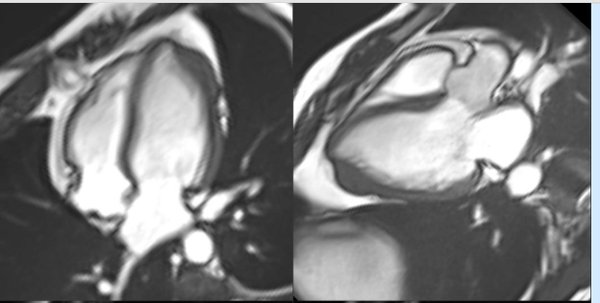

A common clinical presentation of LBBB induced cardiomyopathy is described in this post. It is always dilemma that if LBBB is cause or effect of dilated cardiomyopathy. However CMR can help in differentiating it from other causes and also in predicting response to device therapy. Utilise CMR to the fullest.

Cardiomyopathy